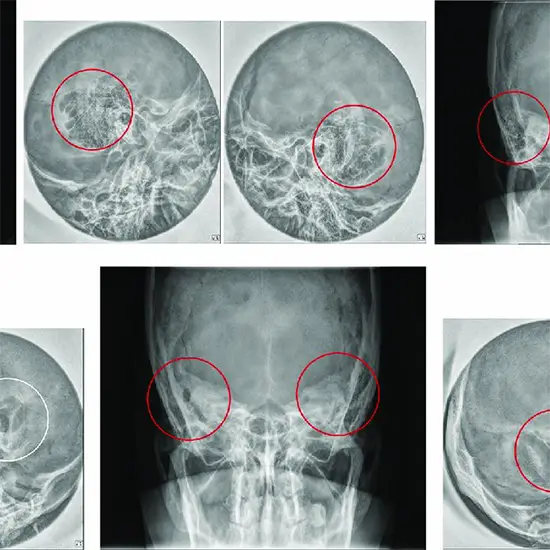

X-Ray of the right ear AP/ Lateral view uses a small amount of radiation to create pictures of the right ear from the front and the side to detect problems in the right ear such as infection, pain, lesion, etc.

Why Do an X-Ray of the Right Ear in AP and Lateral View?

• Doctors recommend this x-ray procedure to assess the right ear anatomy for finding out the problems such as

• Suspicious lesions

• The patient exhibits signs of ear pain, swelling, and infection to find the cause of right ear discomfort and infection.